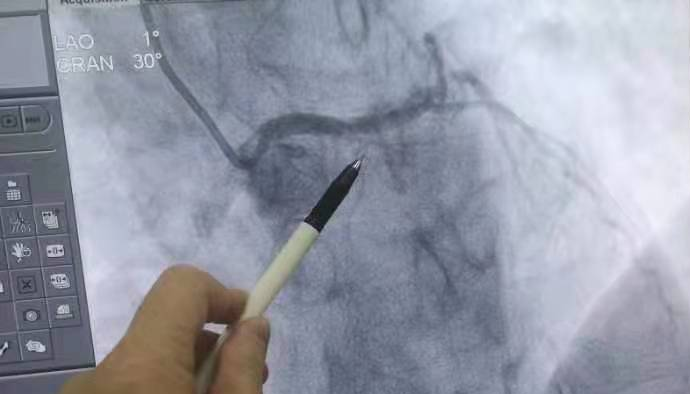

• 西藏阜康醫(yī)院為急性心肌梗塞患者開辟綠色救治通道

2022年11月15日,西藏阜康醫(yī)院心血管內(nèi)科門診接診了一名患者,患者主訴胸悶、胸痛4小時(shí)。通過心電圖檢查,檢查結(jié)果顯示:急性心肌梗塞(廣泛性前壁)。接診醫(yī)生為患者及患者家屬交代了病情的危險(xiǎn)性及預(yù)后等

發(fā)布時(shí)間:2022-11-17 作者: 王星懿

西藏阜康醫(yī)院為急性心肌梗塞患者開辟綠色救治通道